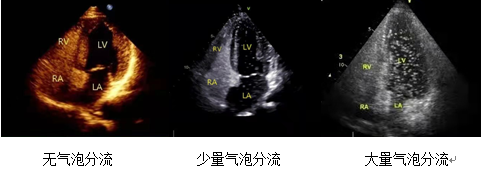

经临床医生判断,齐医附属二院超声科为李先生安排了右心声学造影检查。从下图可知,本来有一墙之隔的左心房和右心房间,出现了一个“通道”,这个“通道”就是未关闭的卵圆孔,它使得大量气泡从右心到达左心。原来,造成李先生多年头痛不断的罪魁祸首就是这个原本应该关闭的卵圆孔。

一个特殊的检查—右心声学造影。右心声学造影技术是经外周静脉注入造影剂,根据造影剂气泡的显影情况来协助诊断的检查方法。造影剂气泡直径>10μm,平均约15μm,按照正常途径不能通过肺毛细血管网,不进入左心系统。因此我们可以根据显影顺序、途径和时间对某些结构和血流异常做出诊断和鉴别诊断。如果左右心系统存在异常通道,那么注入造影剂后左心腔会出现不同程度的微泡显影,我们因此能轻松找到异常通道所在,可协助确定有无卵圆孔未闭 、房间隔缺损、肺动静脉瘘、永存左上腔静脉等异常。